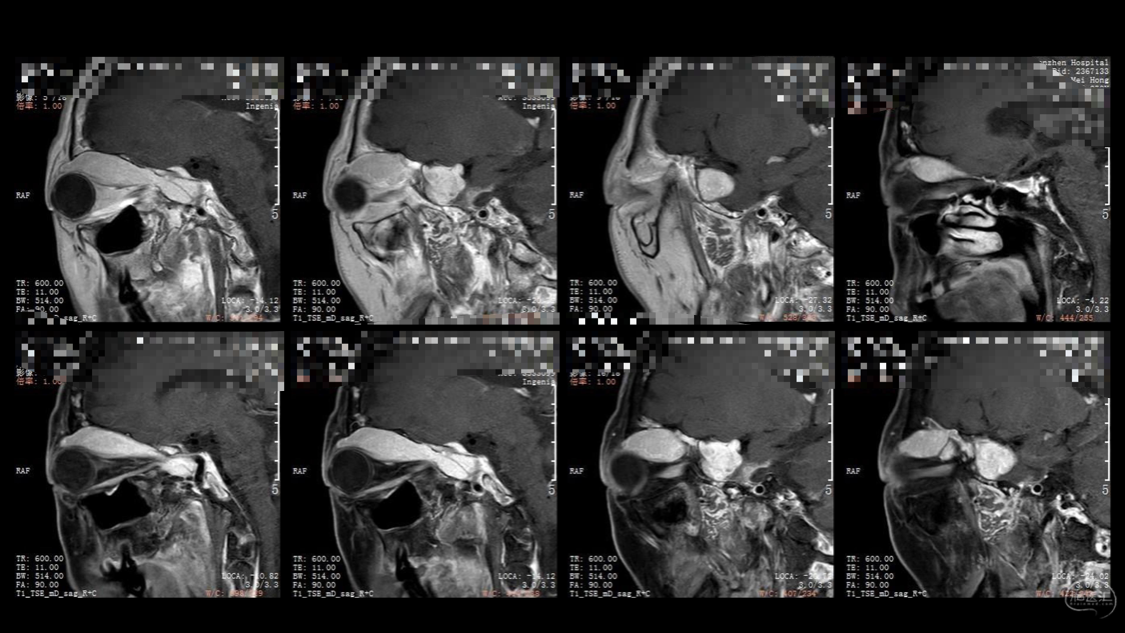

陈保东教授手术作品-右眶内及海绵窦旁孤立性纤维瘤